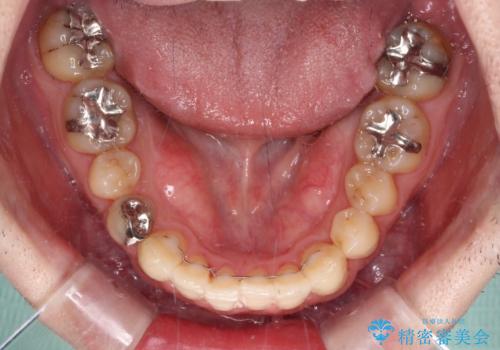

- デコボコした前歯をセラミックできれいに揃えたいとのことで来院された患者様です。

歯を削って整えることは簡単ですが、健全な歯を削って後悔してからでは遅いため、矯正治療を提案しました。

はじめは矯正治療の期間が長いことに悩んでいらっしゃいましたが、ある程度整えば満足するだろうとのことで、インビザラインにて矯正治療を行うこととしました。

左上の犬歯が欠損しているため、正中の位置や奥歯の咬み合わせが理想的にならない点を了承していただきました。